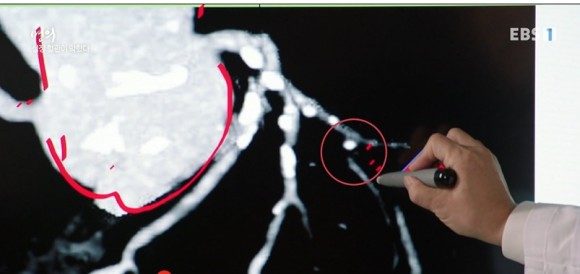

경동맥이 막히는 환자의 초음파 사진과 MRI

가장 간단하고 정확하게 혈관의 이상을 알 수 있는 초음파 검사와 MRI 검사를 실시해 보았습니다. 심장에서 뇌로 가는 혈관은 4개인데 그 중 양쪽 경동맥에서 뇌혈액 공급량의 80%를 담당합니다. 검사상 경동맥의 일부가 좁아져 있는 것이 보입니다.

경동맥은 내막, 중막, 외막의 3중으로 되어 있지만 중요한 것은 혈관벽 두께입니다. 건강한 사람은 내막과 중막 두께를 합치면 0.5~0.9mm인데 만약 1mm가 넘으면 찌꺼기가 쌓여 동맥경화 상태로 봐야 합니다. (심근경색의 2배, 뇌졸중의 5배 증가)